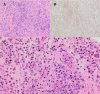

Figure 1. Cervical CT of traumatic fracture and osteolytic lesion

(A) Left parasagittal cervical CT demonstrating osteolytic lesion (red arrows) at cervical 6 and 7 levels. (B) Mid-sagittal cervical CT cervical 7 vertebral body fracture without compression of the spinal cord. (C) Axial CT at the level of cervical 6 demonstrating osteolytic lesion originating at the left facet joint and abutting the left vertebral foramen. (D) Axial CT at the level of cervical 7 demonstrating an osteolytic lesion originating at the left facet joint with visualization of right laminar fracture and partial visualization of left laminar fracture. (E) Axial CT at the level of cervical 7 better demonstrating left laminar fracture CT: computed tomography